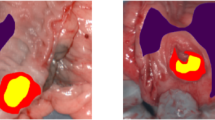

Fluorescence microscopic analysis of tumour tissue, taken 5 min, 2, 6 and 24 h after administration of the compounds, revealed a shifting pattern, as a function of time, in the localisation of labelled lipoproteins and hypericin. At 5 min, DiOC18 and hypericin were still confined to the luminal space of tumoral blood vessels (Figure 5A), as shown in separate experiments with FITC-dextran that was injected 2 min before killing the animals (results not shown). Figure 5B shows the situation after 2 h, where red (hypericin) and green (DiOC18) fluorescence are apparent in the vessels and in the perivascular region. Conversely, at 24 h, a more homogeneous distribution is observed for hypericin in contrast to DiOC18-labelled lipoproteins that show an irregular spreading (Figure 5C).

Fluorescence photomicrographs of 5 μm RIF-1 mouse tumour sections sampled at 5 min (A), 2 h (B) and 24 h (C) after i.v. injection of 5 mg kg−1 hypericin (red fluorescence) and 5 mg kg−1 DiOC18-labelled lipoproteins (green fluorescence). Overlay pictures show the combination of individual photomicrographs of hypericin in the left column, and of DiOC18 in the right column. Scale bar=100 μ M.